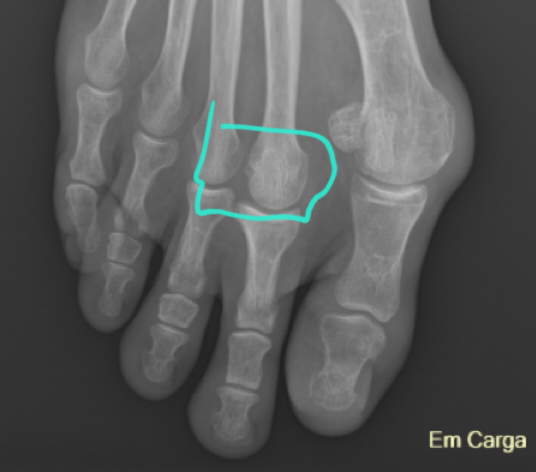

Again, from a total layman's view (who has seen these kinds of images and gone through 2 successful surgeries), the actual big toe halux valagus doesn't look too bad, which is circled in white, but that weird protrusion circled in red grabs attention. Looks like the joint of the big toe is clean, no spurs, no arthritis in there or anything. Your pain @Laurs is coming from the area between the big toe and second toe, is it not? Could it be from that 'blob' in between there? Dunno. Could a surgeon just clear that out of there?🤔

Hi @jeff, thanks so much for paying such good attention :flowers: , and yes, when i saw the X-rays for the first time at the consult with the first ortho, i also asked about that round protruding 'thing.' She then explained it was like a patella on the knee, i think it's called the sesamoid bone. And yes Jeff, the sensitive part is between toes 2 and 3. I have been doing some research and think it's a good idea to tell the ortho tomorrow that i have had psoriasis since i was a baby, my dad had it big time. I never had it bad, just elbows and knees when i was small, and scalp and big toe nails (half way only) when i was in my 30s. Though when i went completely gluten free, it all went away, more or less. I want to ask him if it's a good idea to explore if it could be psoriatic arthritis, i understand that there might be an indication from X-rays and MRI, and they can do further tests, blood and joint fluid, to confirm.

The sesamoids are right where they belong, being part of a tendon system. What has happened is that the 1st metatarsal has gradually moved "inward". Instead of its head being centered over the sesamoids, it is now 'off-center', and severely so. That muscle/tendon system is now functioning like a bow string to reinforce and induce progression of the deformity. The only fix for this is surgery to restore the metatarsal position. That doesn't mean that you need to have surgery, only that surgery is the only possible way to correct the issue. This is an extremely common finding. Most people get on well with this problem.

The deformity is cause by many years of over-pronation while walking.

It looks to me like you may have some instability in the area of the Navicular/1st cuneiform joint, but only a physical examination and gait analysis would tell for sure. If so, this would very definitely contribute to over-pronation.

That "blob" isn't a problem, or so easy to remove.

You might have a nerve entrapment, which is extremely common. More common in Right foot in UK and Left foot in USA. I have a pet theory about clutch use which might explain the pattern. We did a cadaver study on these problems in school, finding such lesions in about half the feet we looked at. Most were asymptomatic, I'd guess. Sort of like a problem just sitting there, waiting for enough of an insult/trauma to flare them up.